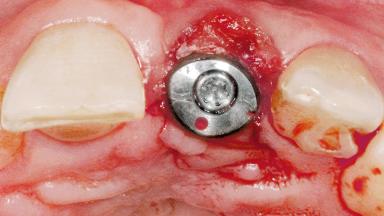

Late Flapless Placement of an Implant in a Maxillary Left Central Incisor Site

Type of Implants One-Piece

Attachment One-Piece

Bone Volume Deficient horizontally, requiring prior grafting